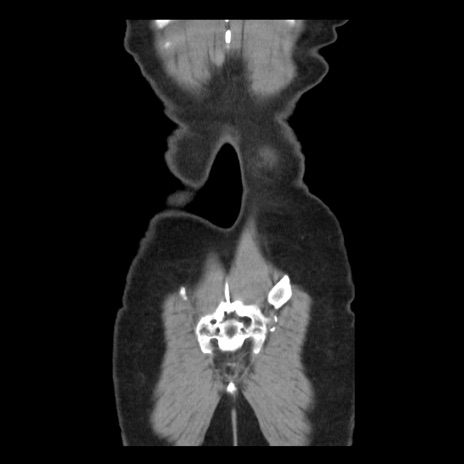

矢状断像